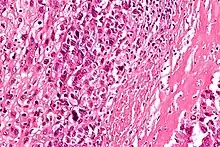

High-magnification micrograph showing osteoid formation in an osteosarcoma H&E stain

Microscopically: The characteristic feature of osteosarcoma is presence of osteoid (bone formation) within the tumor. Tumor cells are very pleomorphic (anaplastic), some are giant, numerous atypical mitoses. These cells produce osteoid describing irregular trabeculae (amorphous, eosinophilic/pink) with or without central calcification (hematoxylinophilic/blue, granular)—tumor bone. Tumor cells are included in the osteoid matrix. Depending on the features of the tumor cells present (whether they resemble bone cells, cartilage cells, or fibroblast cells), the tumor can be subclassified. Osteosarcomas may exhibit multinucleated osteoclast-like giant cells.[21]